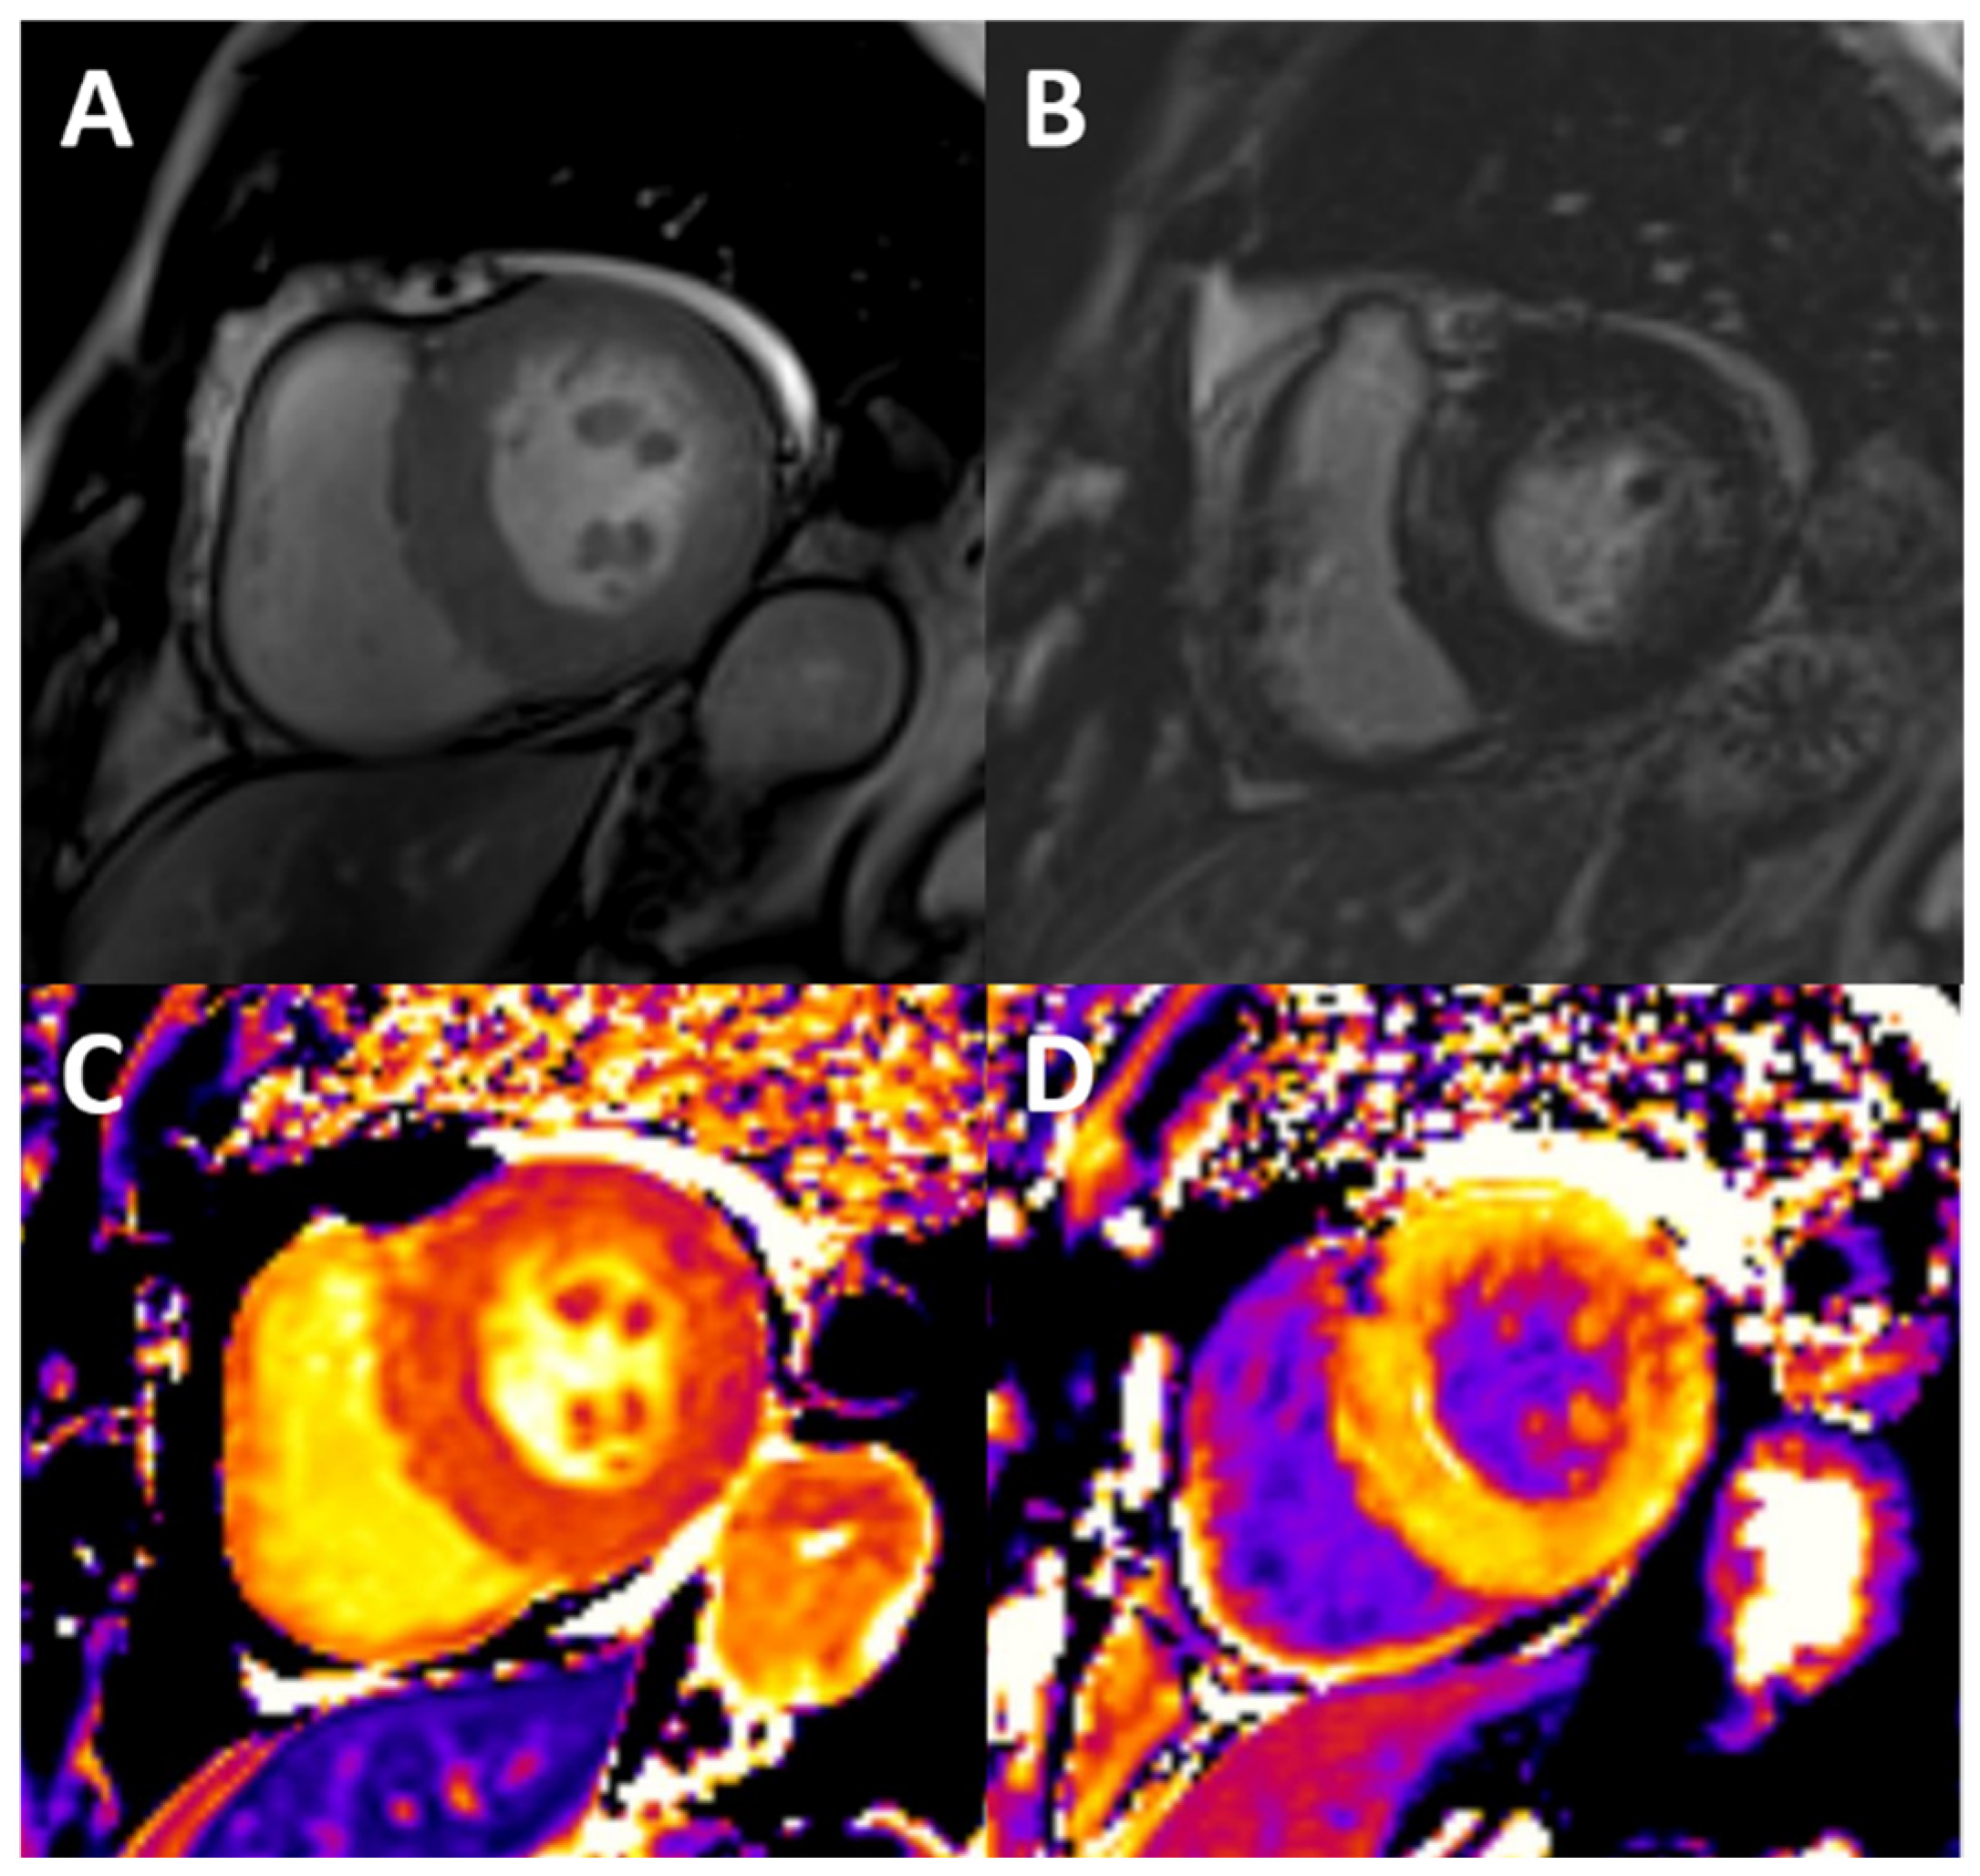

Figure 3.

Typical findings of uremic cardiomyopathy with CMR. The patient presents with mild pericardial effusion, severe concentric LVH with hypertrophy of papillary muscles (A), diffuse intramyocardial LGE (B), and diffuse fibrosis, as shown by high values of native T1 (C) and ECV (post contrast T1, D).